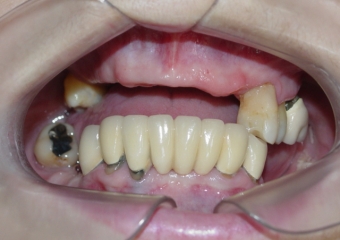

Sorriso final do caso terminado em abril de 2012